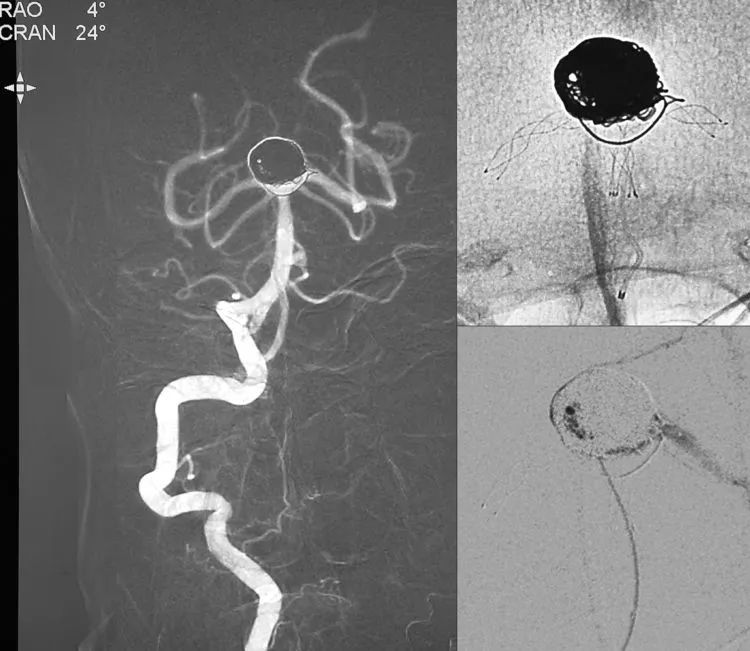

右椎动脉工作位和侧位造影显示动脉瘤完全闭塞,右大脑后动脉不显影跟来自右颈内-后交通动脉的血流对冲有关,不需担心:

将造影管移入左椎动脉再次造影,显示动脉瘤连同子瘤(红箭)完全闭塞,双侧大脑后动脉及小脑上动脉畅通;蒙片可见弹簧圈在瘤腔内铸型致密,瘤颈处膨出的弹簧圈被Y型支架贴附于基底动脉分叉处,形成铆钉帽: